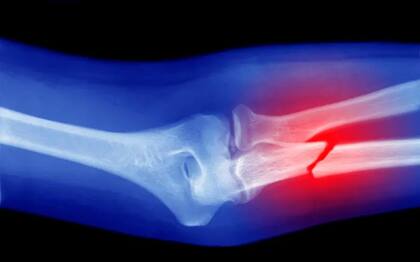

El hueso es otro tejido que puede regenerarse. Si alguna vez te has roto un hueso, sabrás que este se repara y (con el tiempo) puede recuperar la función. Este proceso de reparación de la fractura lleva de seis a ocho semanas. Pero el proceso de regeneración de la arquitectura y la fuerza del hueso continúa durante meses y años después de esta fecha.

Sin embargo, con el aumento de la edad y en las mujeres posmenopáusicas, este proceso se ralentiza y el hueso puede no regenerarse a su fuerza o estructura previas.